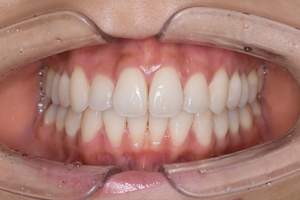

歯石除去

治療前

治療後

| 年齢 | 43歳・男性 |

| 主訴 | 歯石をとりたい |

| 治療内容 | 歯石除去 |

| 治療期間 | 30分 |

| 費用 | 約2,000円 |

| リスク・副作用 | ・歯ぐきの炎症が強いと歯石を取る際に出血することがあります ・処置後に歯がしみることがあります ・歯と歯の間に隙間ができるので、息が漏れ発音しにくいと感じることがあります ・歯ぐきの炎症が軽減すると歯ぐきが引き締まり、歯が長く見えることがあります |